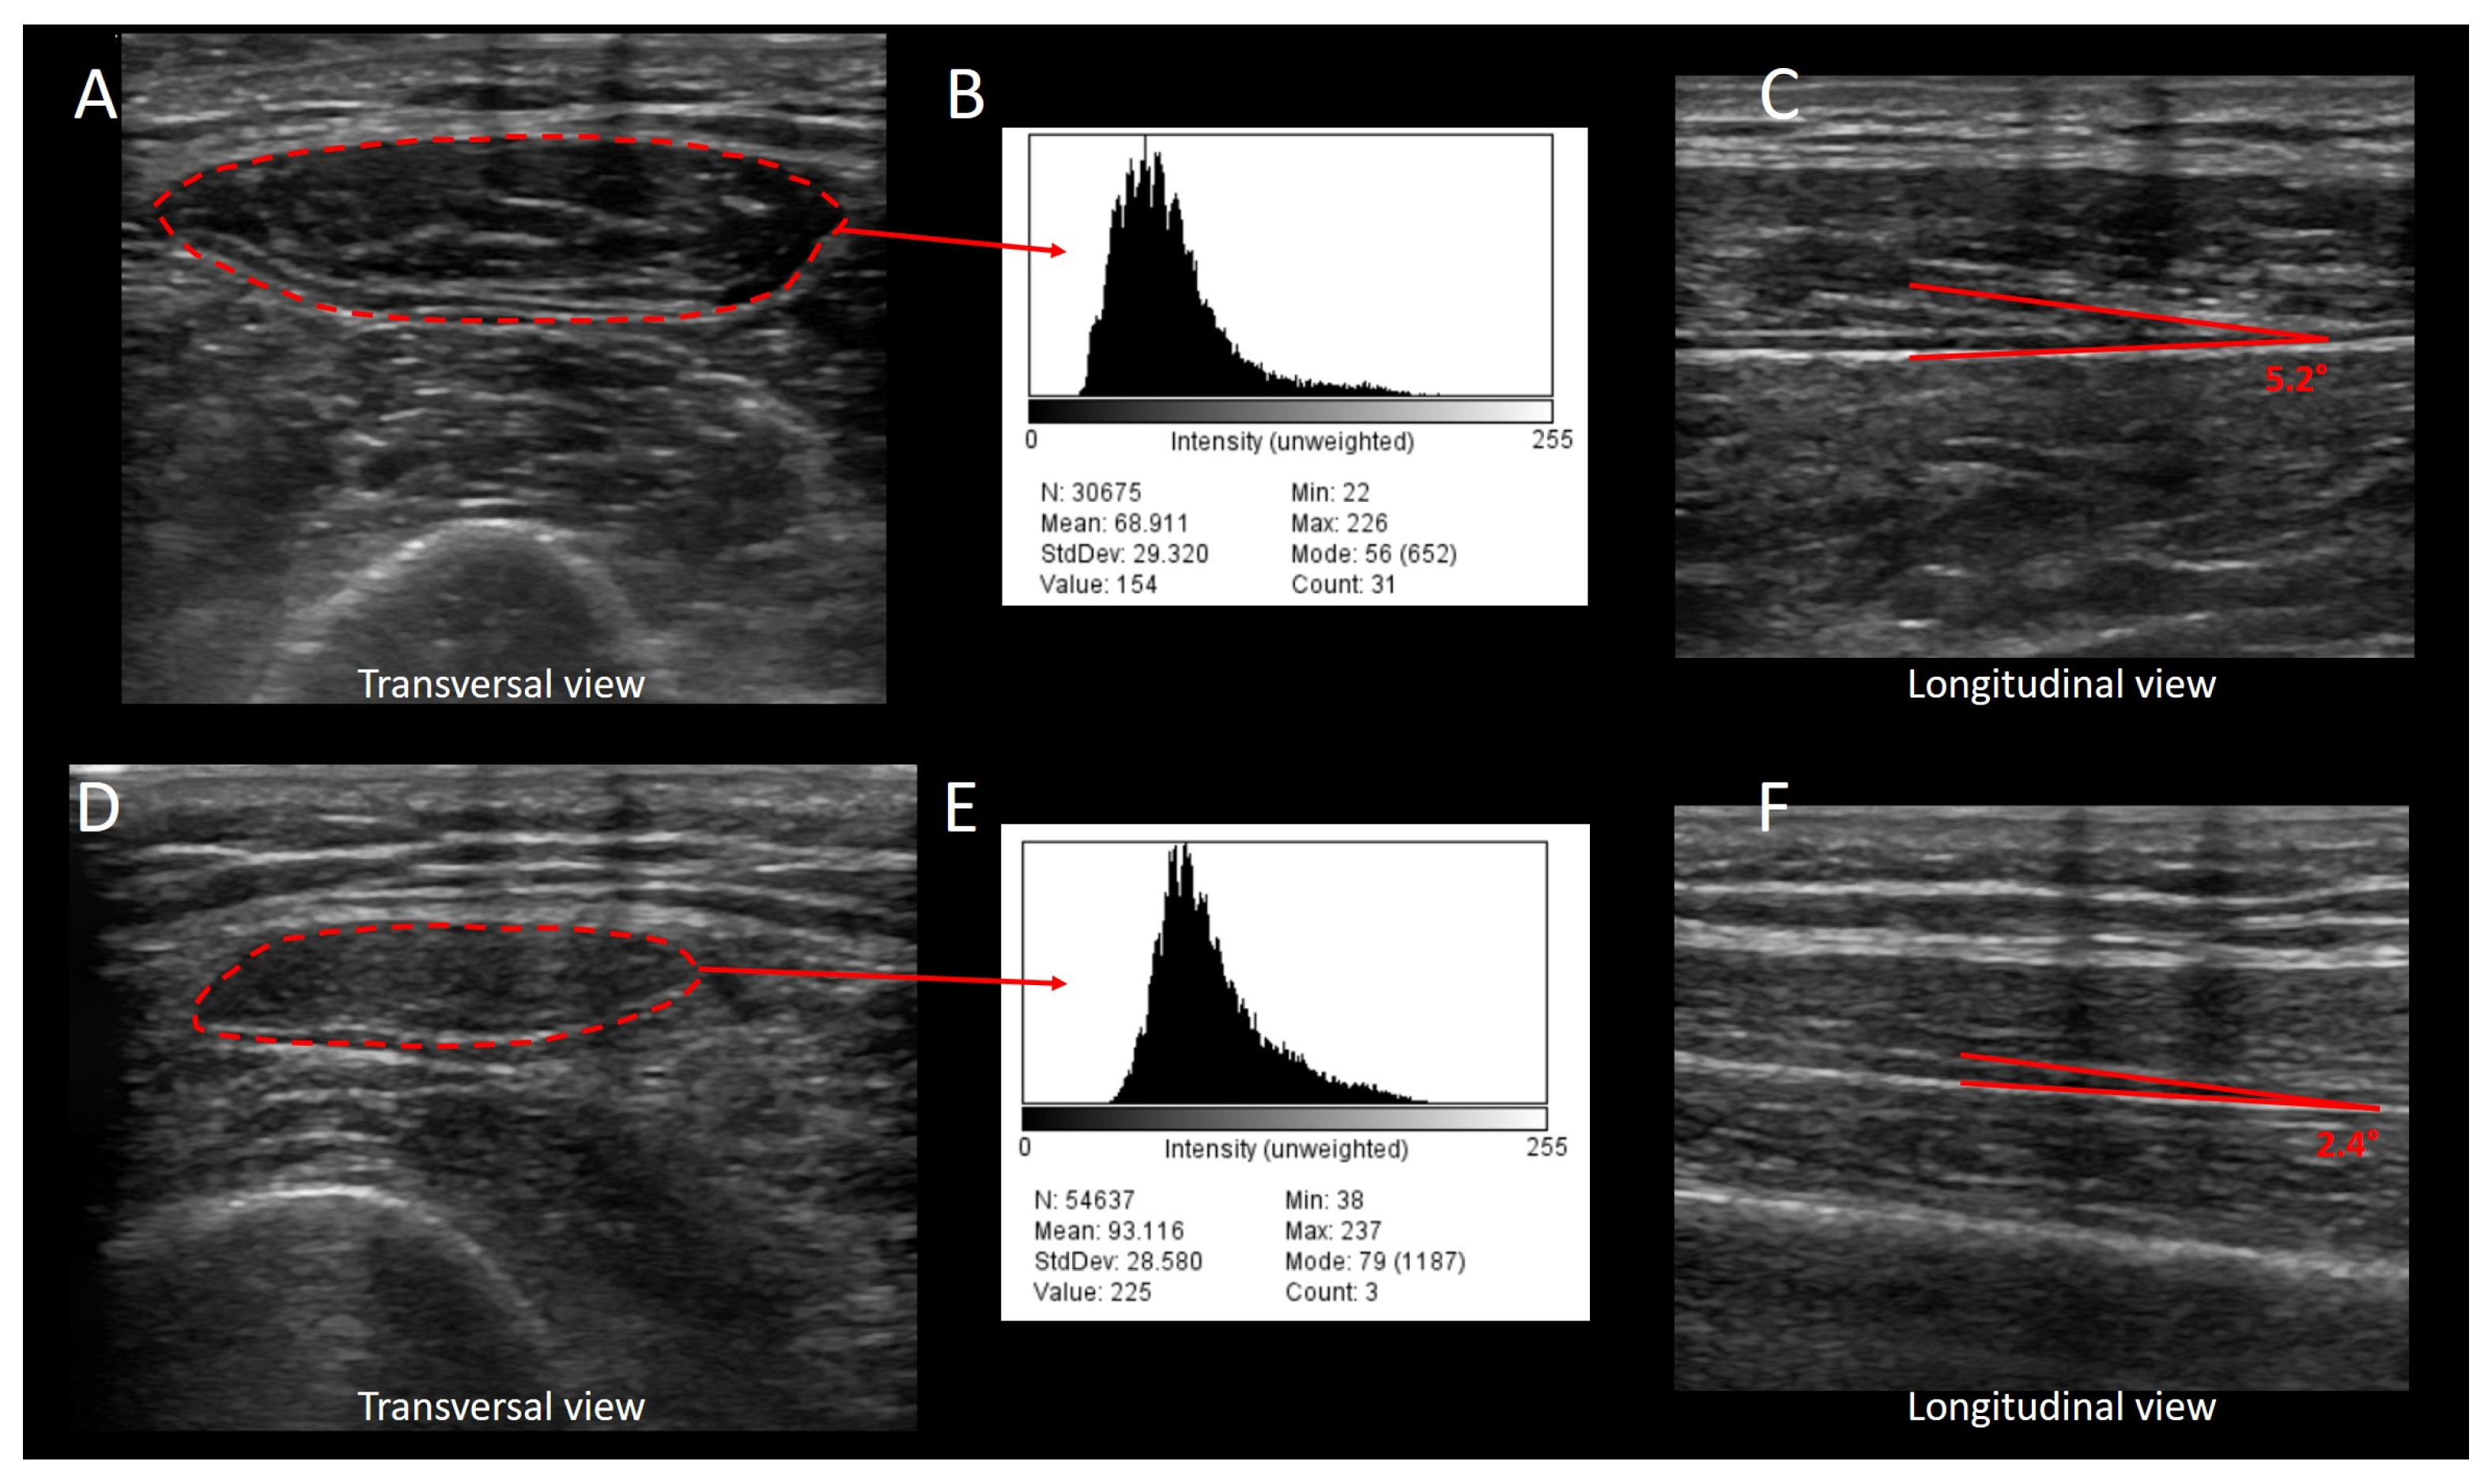

- Albayda, J.; van Alfen, N. Diagnostic Value of Muscle Ultrasound for Myopathies and Myositis. Curr. Rheumatol. Rep. 2020, 22, 82. [Google Scholar] [CrossRef]

- Pillen, S.; van Keimpema, M.; Nievelstein, R.A.; Verrips, A.; van Kruijsbergen-Raijmann, W.; Zwarts, M.J. Skeletal muscle ultrasonography: Visual versus quantitative evaluation. Ultrasound Med. Biol. 2006, 32, 1315–1321. [Google Scholar] [CrossRef]

- Schneider, C.A.; Rasband, W.S.; Eliceiri, K.W. NIH Image to ImageJ: 25 years of image analysis. Nat. Methods 2012, 9, 671–675. [Google Scholar] [CrossRef] [PubMed]

- Harris-Love, M.O.; Seamon, B.A.; Teixeira, C.; Ismail, C. Ultrasound estimates of muscle quality in older adults: Reliability and comparison of Photoshop and ImageJ for the grayscale analysis of muscle echogenicity. PeerJ 2016, 4, e1721. [Google Scholar] [CrossRef] [PubMed]

- Crawford, S.K.; Lee, K.S.; Bashford, G.R.; Heiderscheit, B.C. Spatial-frequency Analysis of the Anatomical Differences in Hamstring Muscles. Ultrason. Imaging 2021, 43, 100–108. [Google Scholar] [CrossRef] [PubMed]